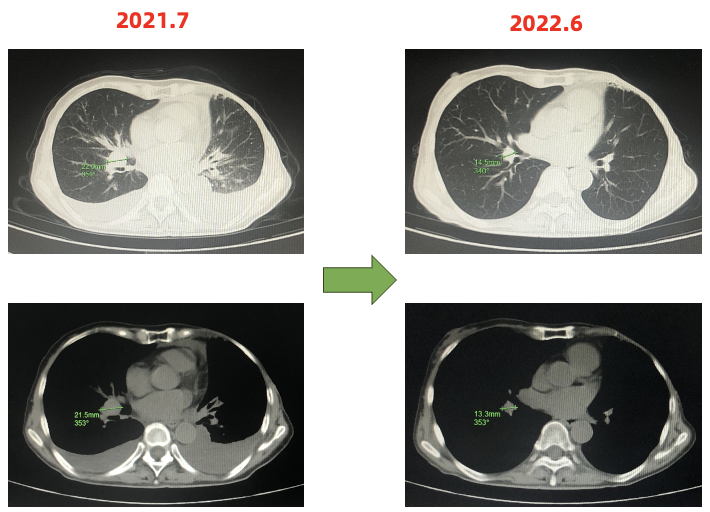

疗效评估:部分缓解(PR)

一线PFS:15月